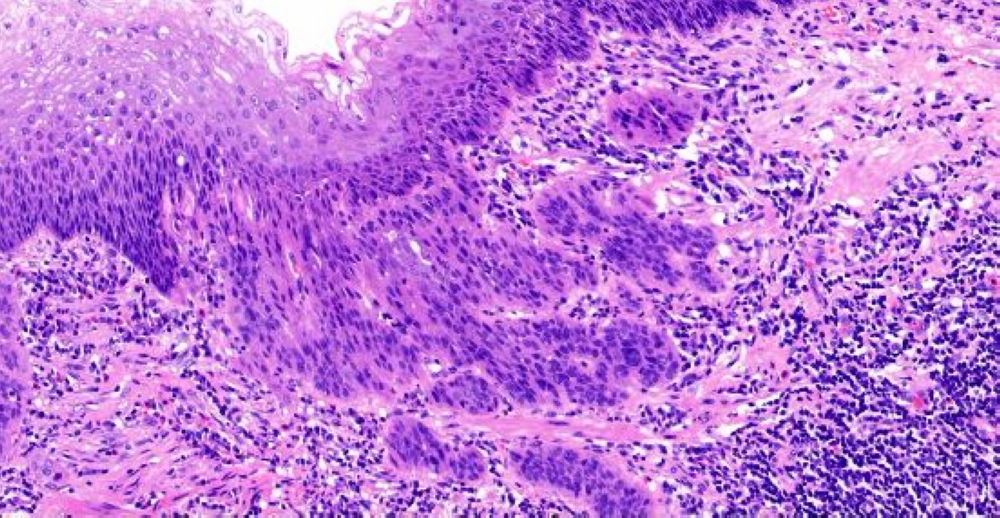

小土豆跟着农人老师学本领-食道手术切除 粘膜表面鳞状上皮缺乏异型性 基底部细胞排列紊乱 浸润性生长  鳞癌